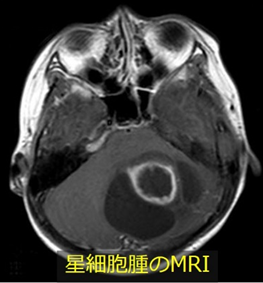

神経細胞を支える役割の神経膠細胞(グリア細胞)の一種である星細胞から発生する腫瘍です。

良性の性格を持つことが多く、大脳や小脳に生じた腫瘍では全摘出することで完治が望めます。しかしながら、脳幹や視床、視神経などに発生した場合には手術が困難であり、放射線治療や化学療法を行なっても治癒困難なことがあります。また、悪性度の高い群も稀にあり、このような場合も放射線治療や化学療法を行いますが治療が難しい疾患の一つです。